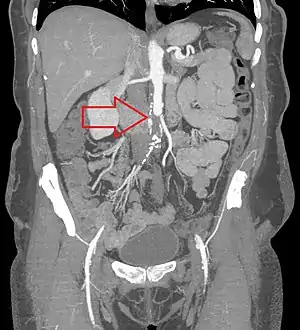

CT angiogram showing a complete blockage or the aorta (red arrow) with the lower limbs supplied by collaterals | |